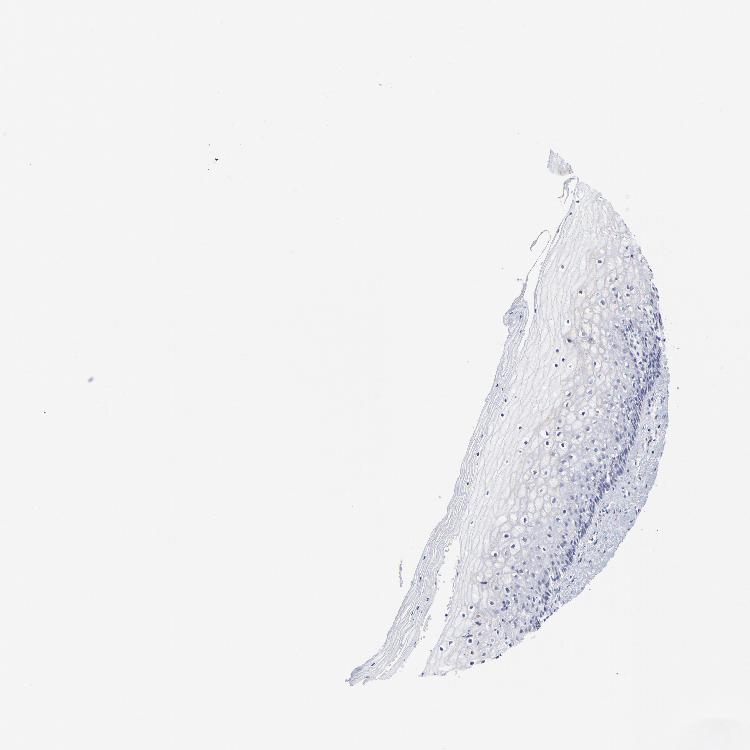

VAGINA - Antibody stainingi

Antibody staining in the annotated cell types in the current human tissue is reported as not detected, low, medium, or high, based on conventional immunohistochemistry profiling in selected tissues. This score is based on the combination of the staining intensity and fraction of stained cells.

Each image is clickable and will lead to virtual microscopy that enables deeper exploration of all samples and also displays staining intensity scores, fraction scores and subcellular localization as well as patient and tissue information for each sample.

Antibody HPA003341

Squamous epithelial cells Not detected